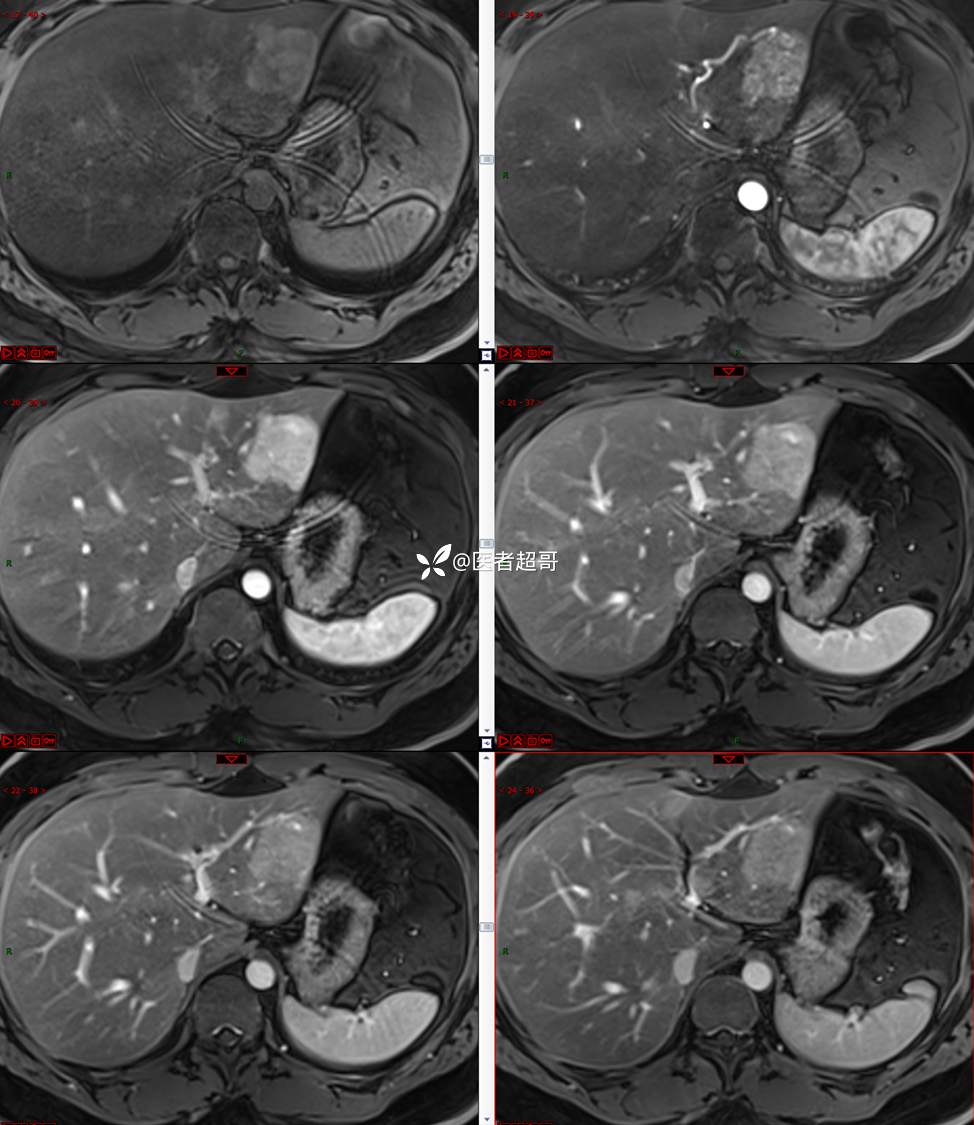

【影诊笔记800】青年男性,肝脏占位,特殊对比剂提示富血供,您能想到啥?有结果!

男,31y

主 诉:发现肝占位性病变5天。

现病史:患者缘于5天前体检时发现肝占位性病变,未予以特殊处置。现患者为求系统诊治就诊于我院,行普美显提示:肝左叶富血供占位,请结合临床及其他检查,肝多发血管瘤,脂肪肝,肝囊肿,请结合临床。门诊以“肝占位性病变”收入我科。病程中,饮食睡眠可,二便可,近期体重未见明显变化。